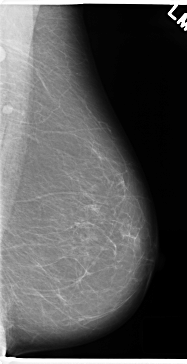

C_0190_1.LEFT_MLO

LEFT_MLO LINES 4720 PIXELS_PER_LINE 2424 BITS_PER_PIXEL 12 RESOLUTION 50 NON_OVERLAY